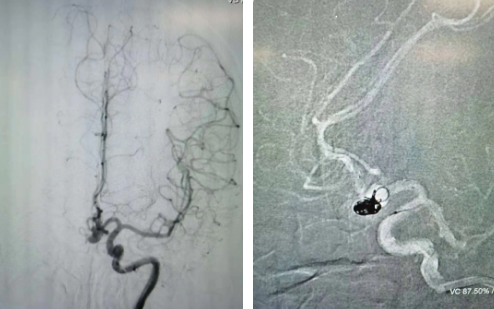

經(jīng)過全面仔細(xì)評估,西安國際醫(yī)學(xué)中心醫(yī)院神經(jīng)外科陸丹醫(yī)生決定采用微創(chuàng)介入進(jìn)行治療。在取得患者及家屬同意后,3月11日,陸丹醫(yī)生為患者行Atlas支架輔助顱內(nèi)動脈瘤栓塞術(shù)。

腦血管較外周血管更為脆弱、迂曲,對術(shù)者的操作技術(shù)及精準(zhǔn)性要求特別高。術(shù)中,陸丹醫(yī)生通過股動脈穿刺、置入微導(dǎo)管,再通過微導(dǎo)管將彈簧圏送入動脈瘤腔內(nèi),利用彈簧圈的機(jī)械閉塞作用,達(dá)到防止動脈瘤破裂的目的。術(shù)后,患者各項(xiàng)生命體征平穩(wěn)。

陸丹醫(yī)生介紹,此次腦科醫(yī)院首次采用Atlas支架輔助進(jìn)行顱內(nèi)動脈瘤栓塞術(shù)。以往動脈瘤栓塞術(shù)中的支架輸送導(dǎo)管較粗,支架順應(yīng)性差,易使載瘤動脈移位,而Atlas支架的輸送導(dǎo)管很細(xì),輸送順滑,同時順應(yīng)性及貼壁性強(qiáng),能夠適應(yīng)迂曲的腦遠(yuǎn)端血管。